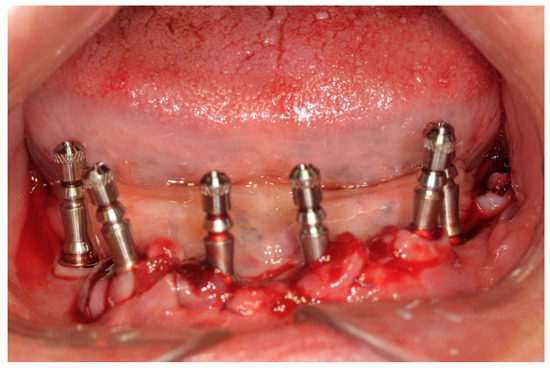

All patients were treated under local anesthesia, and patients received four, five, or six implants in the mandible according to the prosthetic treatment plan. In the case of tooth extraction sites, a periodontal probe was used to assess the integrity of the extraction socket’s bony walls and of the adjacent bone peaks to evaluate the feasibility of an immediate implant (Figure 2).

Figure 2. Operative site after tooth extractions.